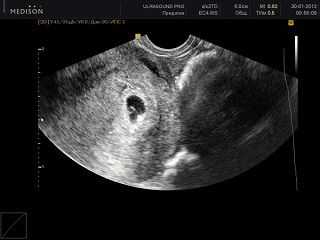

УЗИ на 5 неделе беременности

Чаще всего УЗИ на этой неделе делают с целью подтверждения беременности. Как правило, исследование проводят трансвагинальным способом, так как плод еще совсем крохотный, а данная методика позволяет провести более детальный осмотр.

Одной из важных задач УЗИ в это время является оценка развития сердца ребенка:

- во время осмотра врач замеряет частоту сердечных сокращений малыша, которая должна быть 150-160 ударов в минуту;

- врач фиксирует размеры плода, чтобы установить точный срок беременности, а также вероятную дату зачатия, к сожалению, эти данные при УЗИ на 5 эмбриональной неделе беременности часто не совсем достоверны;

- специалист сможет точно определить, будет ли у вас один ребенок или же двойня, или даже тройня.

Еще одной причиной для данного обследования является подозрение на внематочную беременность. Это осложнение можно заподозрить из-за кровянистых выделений и сильных болей внизу живота, либо же по результатам анализов крови на гормон ХГЧ. Обычно в таких случаях содержание этого гормона бывает ниже нормы.

Ультразвуковое исследование

Именно на этой неделе начинает работу сердце, врач, сравнивая активность плода, сердечный ритм и в конце составит заключение. Даже размер плода пока измеряется как маленькое коричневое пятно.

УЗИ на 5 неделе

Если на таком раннем сроке доктор не уверен в наличии беременности, возможно прибегнуть к помощи УЗИ. Ультразвуковое исследование покажет количество плодных яиц, локализацию плода в полости матки, размеры матки. На УЗИ обследовании уже можно увидеть место формирования ручек и ножек вашего будущего ребенка.

В яичниках все еще визуализируется желтое тело, которое обеспечивает гармоничное протекание и развитие беременности, при увеличенных размерах желтого тела проводят дополнительные обследования для выявления кисты желтого тела.

В полости матки просматривается несколько увеличенный в размерах желточный мешок, на 5 неделе беременности его размеры составляют 3 – 4 мм. Увеличение или уменьшение размеров желточного мешка говорит о возможной патологии развития беременности. Именно по этой причине на ультразвуковом исследовании оценка состояния желточного мешка является важной составляющей.